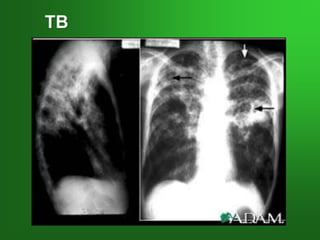

TB